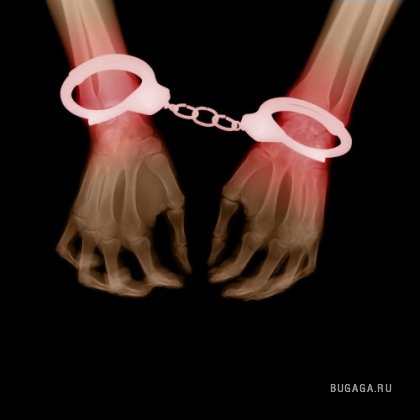

Попался

Попался 2